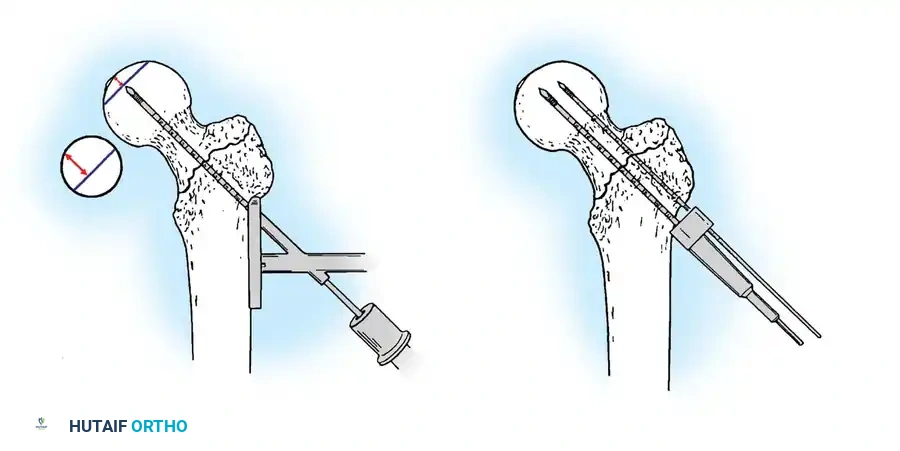

3. Guide Wire Placement

Whether using an SHS or a CMN, accurate placement of the guide wire into the femoral head is the most critical step of the operation.

Insertion of the guide wire. The wire must be positioned centrally in the femoral head on both AP and lateral views.

The Tip-Apex Distance (TAD):

Described by Baumgaertner, the TAD is the sum of the distance from the tip of the lag screw to the apex of the femoral head on both the AP and lateral radiographs. A TAD of less than 25 mm is strongly predictive of successful fixation; a TAD > 25 mm significantly increases the risk of screw cut-out.

4. Reaming and Lag Screw Insertion

Once the guide wire is perfectly positioned, the lateral cortex is opened, and the femoral neck is reamed over the wire.

Reaming of the femoral neck and head over the precisely placed guide wire, preparing the channel for the lag screw.

The lag screw is then inserted. It is crucial not to over-insert the screw, which can penetrate the articular cartilage, nor to under-insert it, which compromises fixation.

After the nail is seated, the proximal lag screw(s) are inserted through the nail into the femoral head, adhering to the same TAD principles.

Proximal locking of the cephalomedullary nail. The targeting guide ensures accurate trajectory into the femoral neck.